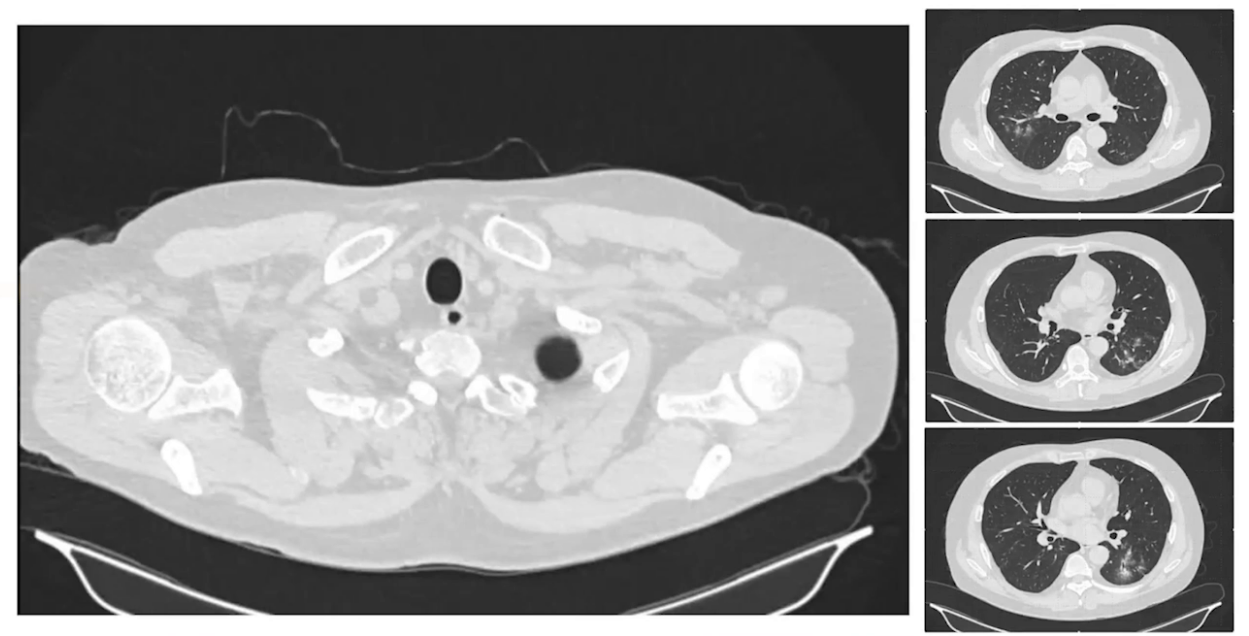

2024.8.4胸部CT:两肺多发边界不清结节影,分布于右上叶后段、左下叶背段及基底段,沿支气管血管束分布,部分病灶可见支气管充气及管壁增厚,提示可能为小叶性肺炎。

8月12日复查胸部CT,两肺病变进展,肺部病变性质改变,出现斑片状不同密度改变,有磨玻璃影和实变,右下叶实变病灶可见支气管扩张。气管镜检查气道内无明显异常,肺泡灌洗液以中性粒细胞升高为主,NGS检测出序列数很高的副流感嗜血杆菌阳性结果,气管镜标本细菌培养、抗酸杆菌和真菌镜检均为阴性,再次复查呼吸道病原体IgG抗体、出血热抗体和CMV抗体均为阴性,血沉和自身抗体也为阴性,肌酐稳定。